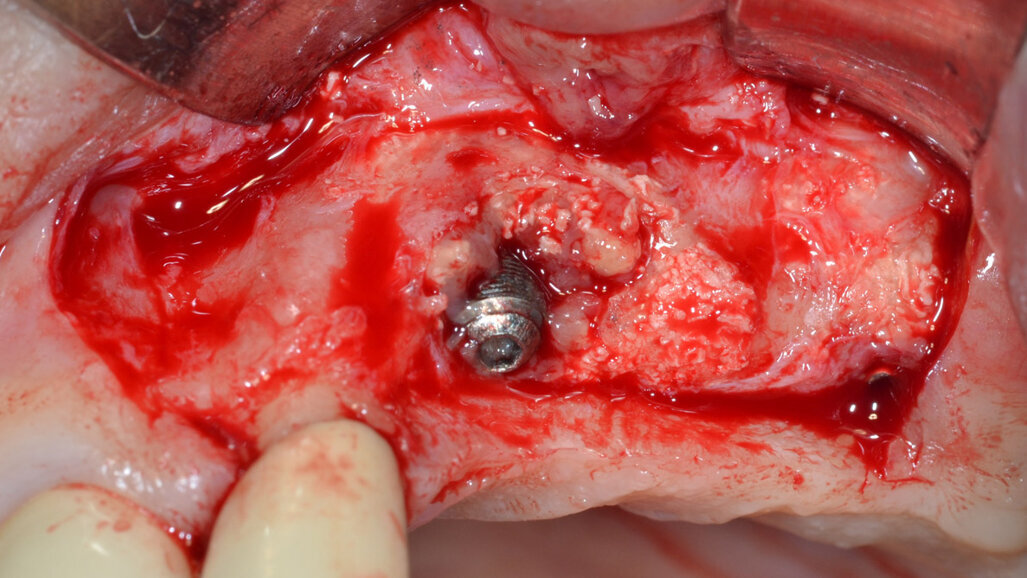

Dopo aver rimosso la protesi fissa e la relativa componentistica, vengono inserite due viti di copertura sterili per consentire una chiusura spontanea dei tessuti molli al fine di poter garantire una chiusura per prima intenzione e una guarigione della ferita chirurgica di tipo sommerso. La procedura chirurgica viene pianificata a distanza di 14 gg. Il primo tempo operatorio consiste nel disegno e nell’elevazione di un lembo di accesso a spessore totale delimitato da un’incisione crestale (effettuata all’ interno della banda di gengiva aderente) e da due incisioni di rilascio verticali leggermente divergenti tra loro (Fig. 3). Al sollevamento del lembo è possibile rilevare un notevole difetto intraosseo peri-implantare; sono inoltre presenti residui di biomateriale non integrato reliquati da un pregresso intervento di rigenerazione ossea (Fig. 4). Il tempo operatorio successivo consiste nel debridement del tessuto di granulazione e dei residui di biomateriale mediante un inserto a ultrasuoni (ES030ACT, Esacrom) (Fig. 5).

Fig. 4 - Presenza di un vasto difetto intraosseo peri-implantare con residui di biomateriale non integrato.